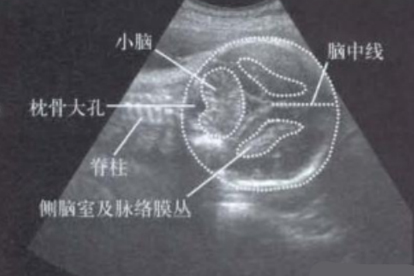

小腦部分切除后可能影響平衡協(xié)調(diào)、精細(xì)動(dòng)作和語(yǔ)言功能,具體表現(xiàn)與切除范圍有關(guān)。小腦是控制運(yùn)動(dòng)協(xié)調(diào)和姿勢(shì)調(diào)節(jié)的重要腦區(qū),手術(shù)干預(yù)需嚴(yán)格評(píng)估適應(yīng)癥。

小腦部分切除后常見(jiàn)影響包括肢體共濟(jì)失調(diào),表現(xiàn)為行走不穩(wěn)、持物不準(zhǔn)?;颊呖赡艹霈F(xiàn)意向性震顫,即接近目標(biāo)時(shí)手部抖動(dòng)加劇。部分病例伴隨構(gòu)音障礙,發(fā)音含糊或語(yǔ)速異常。眼球運(yùn)動(dòng)異常如眼球震顫也可能發(fā)生,影響視覺(jué)追蹤能力。這些癥狀源于小腦對(duì)大腦皮層運(yùn)動(dòng)信號(hào)的調(diào)節(jié)功能受損。